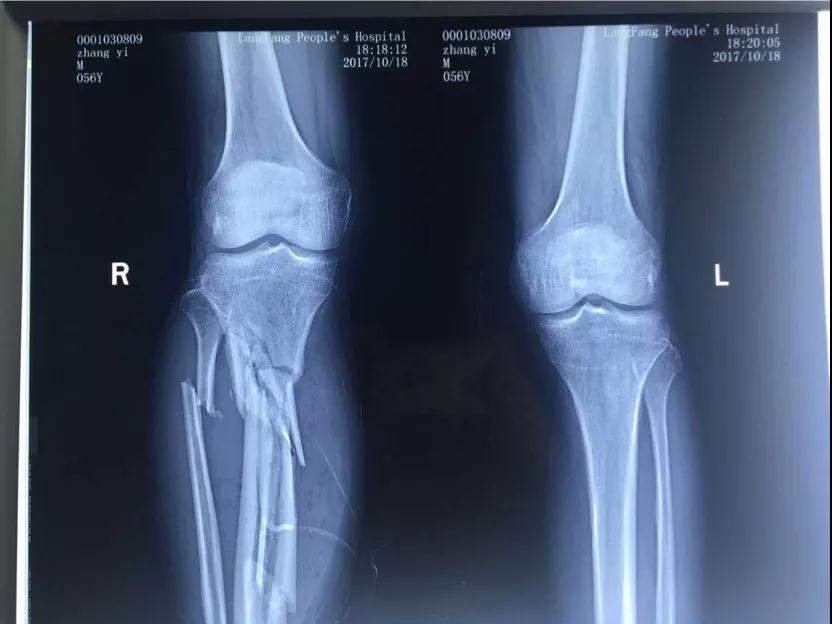

2017年10月18日十九大召開的當天下午五點多鐘,我像往常一樣去師範學院院裏老人居住的地方吃晚飯,此時,早已等待在老人樓下的一輛無牌照車裏出來四個蒙面人將我的腿打斷後逃走,這是十九大召開的的當日,是光天化日之下在大學的校園裏,是當着校園裏的教職工的面有預謀有組織的謀害。住院手術之後該團伙依然繼續到新院區繼續騷擾威脅,楊XX指使醫院會計在未履行任何財務手續的情況下從城南醫院挪用現金一千一百萬元,從兒媳婦XX也屬於城南醫院個人卡河北農信尾號XXXX中轉走五百萬元,此情況已經向安次區刑警隊和廊坊市公安局趙進晉局長報案’,至今至我傷殘和挪用醫院資金幕後指使依然逍遙法外。

2017年10月18日,張院長在廊坊師範學院院內遭受4名歹徒毆打至右腿粉碎性骨折,4名歹徒和背後指使者趙XX 均已落案。